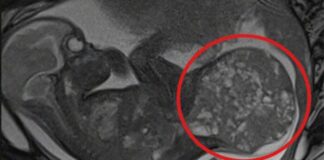

Bebê nasce com tumor que ocupa metade do corpo e é...

Rápida reação da equipe médica foi decisiva para o sucesso da operação; recém-nascida respira sozinha e deve receber alta

Itália- Uma bebê prematura de 30...